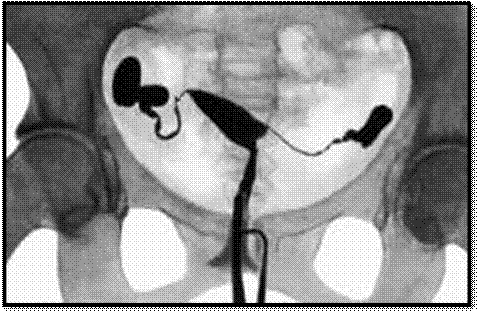

С целью уточнения диагноза миома матки выполняют дополнительные исследования: ультразвуковые, эндоскопические, рентгенологические. Из эндоскопических исследований наиболее часто используют: гистероскопию, кольпо-, цервико-, лапаро- и кульдоскопию. Одновременно оценивают состояние эндометрия и яичников, дифференцируют миому с опухолями придатков матки, забирают материал для цитологической и гистологической верификации диагноза. При постановке диагноза и оценке эффективности лечения важно учитывать дни менструального цикла, осмотры и УЗ-сканирование проводить в динамике, в одни и те же дни цикла.

Рис. №4 Гистеросальпингография